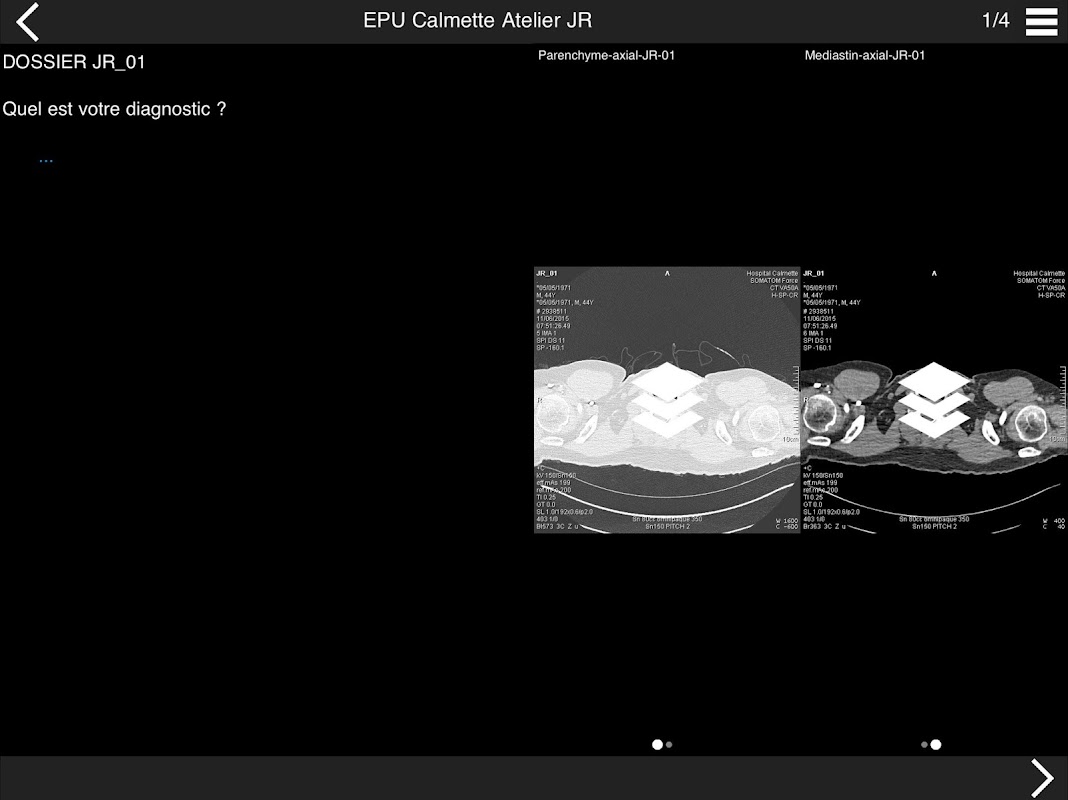

Retrouvez les cas cliniques du Cours intensif de TDM multicoupe du thorax dans cette application.

Thèmes du cours 2017 :

ACTUALISATION DES PROTOCOLES

• DE LA SéMIOLOGIE AU COMPTE-RENDU

* BPCO et nodules pulmonaires : recommandations en 2017

* Pathologie interstitielle : lésions élémentaires et « patterns »

* Pathologie vasculaire et médiastinale

* Oncologie thoracique : bilan standard et introduction à l’étude de l’angiogénèse

* Amiante : images pièges et discordances des secondes lectures.

• INITIATION A L’IMAGERIE CARDIO-THORACIQUE INTEGRéE

* La pathologie que l’on ne peut plus méconnaitre dans le cœur sur un examen

thoracique

Organisé par :

Pr J. REMY - Pr M. REMY-JARDIN

Dr J.B. FAIVRE - Dr F. PONTANA

Hôpital Calmette - CHRU de LILLE